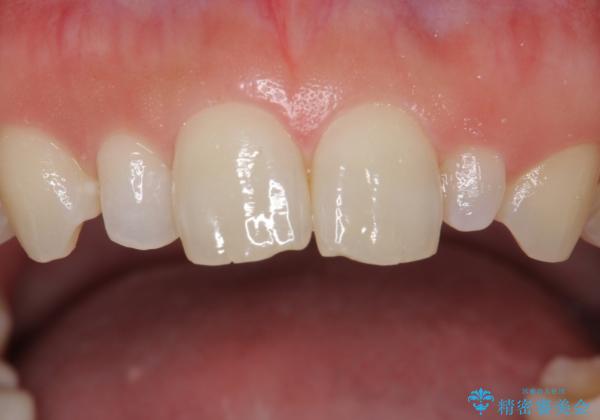

前歯が大きいのが気になる セラミックで整えたい

- 前歯が大きいのを揃えたいとのことでした。

少し削って長さを短くして様子を見ましたが、どうしても気になるとのことでした。

隣の前歯が小さいため、4本被せてバランスをとりました。

4本セラミックにすると大きさだけでなく、色も揃えられるのでおすすめです。

- ジルコニアクラウン(スタンダード) 11万円×4本、仮歯 1万円×4本費用は治療当時の料金となります

歯の向きは悪くなかったため、神経は取らずに治療しました。